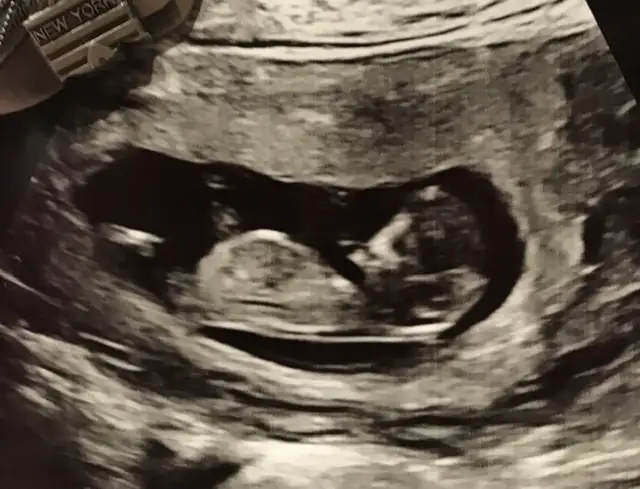

ErkekMerhaba. 11+2’deki USG icin cinsiyet tahmininizi alabilir miyim? İlk goruntu karindan usg, digeri vajinal usg. Tesekkur ederim.

Bizede bi tahmin yapar mısınız ???

Erkek gibiBizede bi tahmin yapar mısınız ???

tatlicincap kız gibi gibi tekrar usg paylaşın

Bugün doktor kıza benzetti ama bakalımErkek gibi

Bende erkeğe benzettimBizede bi tahmin yapar mısınız ???